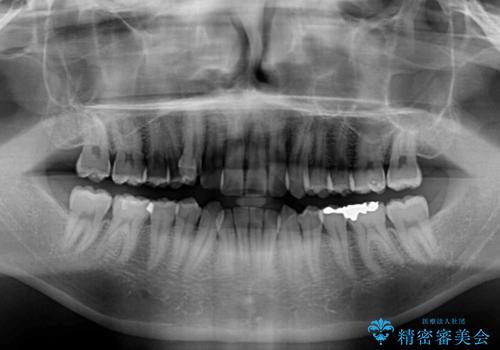

- 前歯のデコボコと右上の八重歯を気にして来院された患者様です。

マウスピース矯正とワイヤー矯正で悩んでいらっしゃいましたが、非常に強い咬合力であることや、お仕事柄不規則な生活リズムになることが多いとのことで、ワイヤー装置にて矯正治療を行うこととしました。

口元が突出する仕上がりとならないように、舌突出癖改善のトレーニングをしっかりと行っていただきながら、矯正治療を進めていくこととしました。